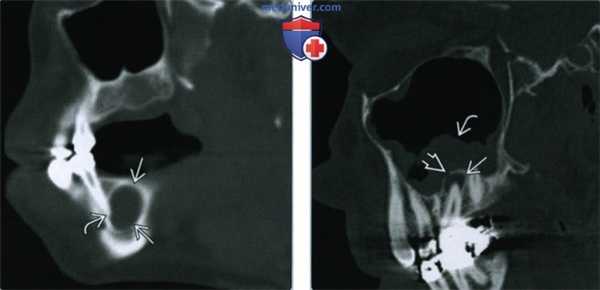

(Слева) На сагиттальной КЛКТ визуализируется крупная радикулярная киста, смещающая дно верхнечелюстной пазухи кверху и занимающая ее нижнюю треть. Обратите внимание на воспалительные изменения пазухи.

(Справа) На профильном срезе (КЛКТ) визуализируется крупная кариозная полостьв нежизнеспособном моляре; также видны два периапикальных абсцесса. Поражение щечного корня приводит к деструкции щечной кортикальной пластинки альвеолярного отростка. Сужение пульповых каналов необходимо отметить как вероятное осложнение эндодонтическою лечения.